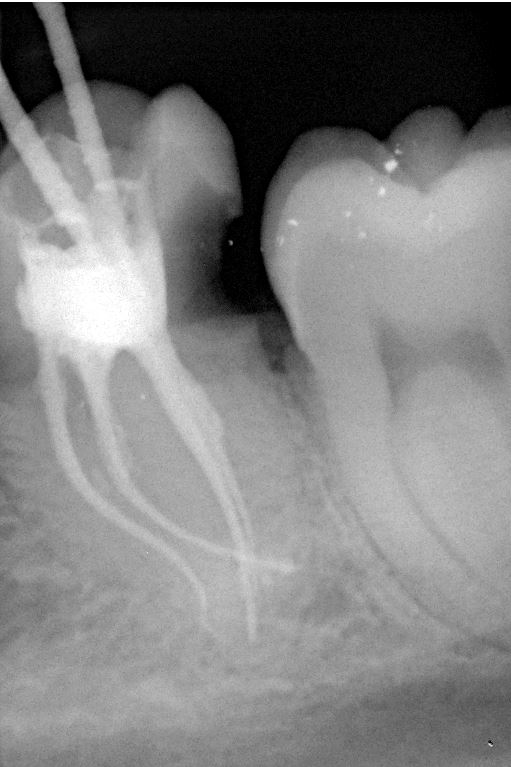

Fallbeispiel für einen komplexen Kanalverlauf

Da die Wurzelkanäle sehr klein sind und sich oft verzweigen, ist es nicht immer einfach, alle Kanäle mit ihren Seitenästen aufzufinden.

Bei der modernen endodontischen Behandlung können durch ein Dentalmikroskop auch kleinere Kanälchen aufbereitet werden, die man auch mit einer Lupenbrille nicht finden würde.

Nur wenn das Wurzelkanalsystem komplett aufgefunden und gereinigt wird, hat eine Wurzelkanalfüllung eine gute Langzeitprognose.